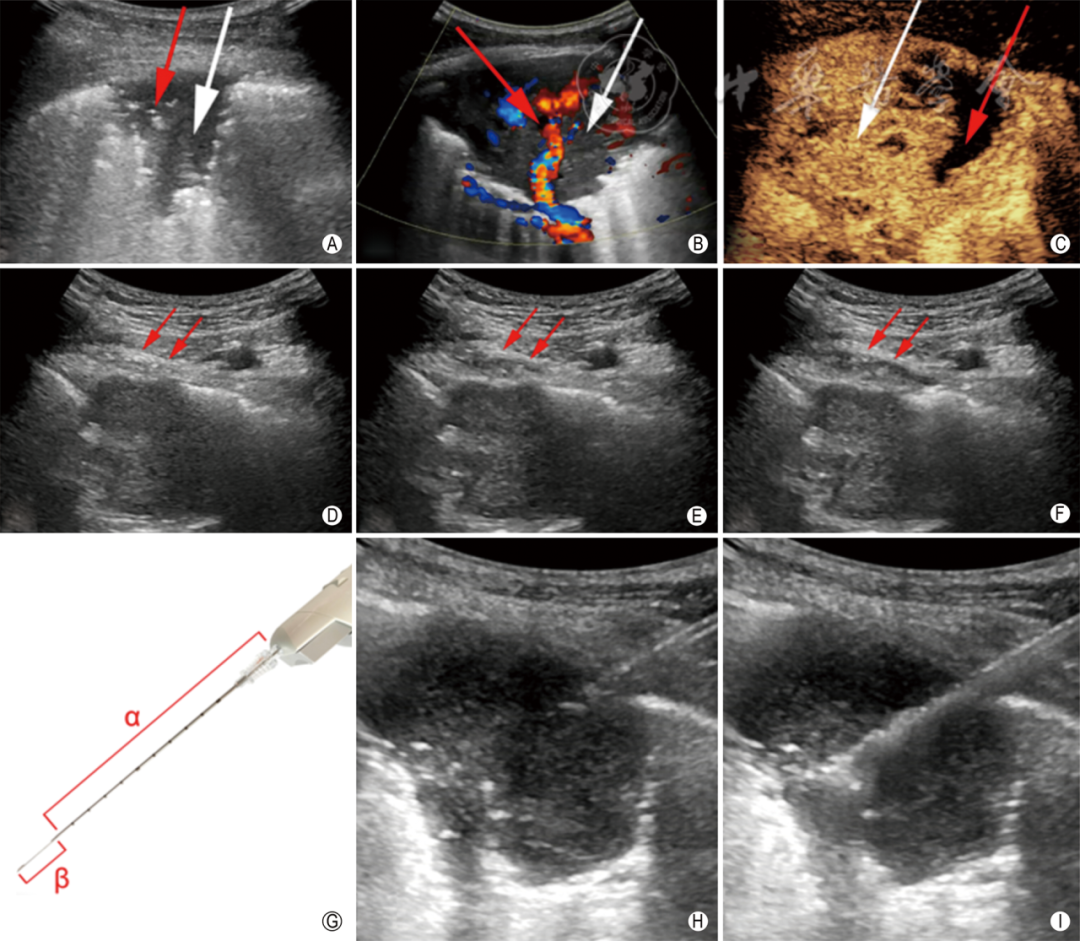

2.病灶形态及其与胸膜夹角:恶性病灶多为球形,与胸膜夹角呈钝角。良性病灶多为楔形,与胸膜夹角呈锐角(图2 A~D 白色箭头所示)。

图2  胸膜下肺病灶的超声特征 A、B:灰阶超声显示胸膜下恶性病灶,与胸壁分界不清,胸膜局限增厚。病灶呈不规则球形,与胸膜夹角呈钝角(A图白色箭头所示,B图α角所示),内未见支气管充气征,后方回声呈“瀑布征”(A图黄色箭头所示,B图白色条带所示);C、D:灰阶超声显示胸膜下良性病灶,边界不清,呈楔形,病灶与胸膜夹角呈锐角(C图白色箭头所示,D图β角所示),内见支气管充气征(C图红色箭头所示,D图白色类圆形所示),病灶后方呈“碎片征”(C图黄色箭头所示,D图白色条带所示);E:彩色多普勒血流成像(CDFI)显示肺动脉分支进入病灶内,频谱多普勒(PWD)示双向高阻力动脉频谱;F:CDFI显示病灶浅部平行于胸膜的血流信号,PWD示单向高阻力动脉频谱,考虑为肋间动脉;G:CDFI显示病灶内血流信号,PWD示单向低阻力动脉频谱,考虑为支气管动脉;H、I:CDFI显示病灶中央血流信号,PWD示阻力极低的动静脉瘘频谱,考虑为肿瘤新生血管;J:多普勒超声模式图显示肺动脉(PA)呈双向高阻力动脉频谱,支气管动脉(BA)呈单向低阻力动脉频谱,肋间动脉(ICA)呈单向高阻力动脉频谱,肿瘤新生血管(TN)呈极低阻力动静脉瘘频谱;K:弹性成像显示病灶以绿色区域为主,评分1分;L:弹性成像显示病灶以绿色及红色区域为主,伴有少量蓝色区域,评分2分;M:弹性成像显示病灶蓝色与绿色区域面积基本一致,评分3分;N:弹性成像显示病灶以蓝色区域为主,评分4分;O:弹性成像显示病灶内及周边均以蓝色为主,评分5分;P:弹性成像显示不连续、平行于胸膜的红绿蓝三色斑点或条带的“水波纹征”,改良弹性成像5分法将其评为1分(图中黄色十字标记病灶位置)

3.回声:良恶性病灶几乎均表现为欠均匀的低回声;支气管充气征多见于良性病灶(图2 C红色箭头所示) 。

4.边缘及后方回声:恶性病灶以膨胀和侵袭生长为特征,边缘更清晰,后方回声增强呈“瀑布征”;良性病灶多为炎性,肺泡逐渐被液体充填,病灶边缘更模糊,呈片状和叠瓦状的“碎片征”(图2 A~D黄色箭头所示)。

5.胸膜侵犯:恶性病灶常侵犯胸膜,表现为局部胸膜增厚,病灶与胸膜分界不清,胸膜滑动征消失(图2 A、B蓝色箭头所示)。需要注意的是肺部慢性炎症随着病程的延长也会造成胸膜侵犯,以结核、机化性肺炎多见。

频谱多普勒(pulsed-wave Doppler,PWD)技术通过测量动脉阻力指数(resistance index,RI),为病灶良恶性鉴别提供血流动力学信息。良性病变主要由肺动脉供血,呈双向高阻力动脉频谱;而恶性病灶主要由支气管动脉和肿瘤内新生血管供血,分别呈单向低阻力动脉频谱和极低阻力的动静脉瘘频谱(图2 E~J)。

超声弹性成像主要包括剪切波成像和应变式成像两类。Ozgokce等研究表明,当剪切波速度>2.47 m/s时可以诊断病灶为恶性,其敏感性和特异性均达到了98%。Sperandeo等依据应变式弹性成像感兴趣区内蓝色(质硬)区域面积百分比评分,以10%、35%、60%、85%为分界线分为0~5级,以4级为临界值时,敏感性和特异性分别为87%和99.7%。除此之外,蓝色区域为恶性的可能性更高,可针对性穿刺活检。

笔者团队提出改良5分法进行应变式弹性成像评分,具体为:病灶几乎全部呈绿色或红色,评为1分;病灶蓝绿相间,以绿色为主,评为2分;病灶蓝绿相间,面积大体相等,评为3分;病灶几乎均为蓝色,只有少量绿色,评为4分;病灶内部和周边均为蓝色,可伴有少量绿色,评为5分,其中恶性病灶多≥4分(图2K~P)。在对170例患者的一项回顾性研究中,获得了88%的敏感性和84%的特异性。